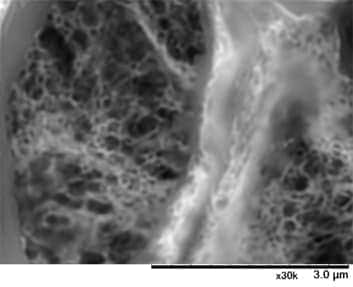

LVSEM image of a PAM-stained glomerulus from a case of Alport syndrome, clearly showing the mesh-work structure in the basement membrane.

Dr. Inaga emphasizes that "As might be expected, 3D images that can be seen stereoscopically under LVSEM, different from conventional TEMs and light microscopes, is very important." She notes "In cases of Alport syndrome, a mesh-work structure occurs in the basement membrane. Previously, diagnosis with a TEM was based on two-dimensional images of the section, and it appeared that the structural configuration might be basket-weave. With the 3D images, it became possible for the first time to really see that it actually is a basket."

Alport syndrome is a hereditary, progressive disease in which characteristic changes occur in the glomerular basement membrane. Similar abnormalities in the glomerular basement membrane can also be seen in thin basement membrane disease. However, in Alport syndrome, these abnormalities can progress to end-stage renal disease in youth, necessitating dialysis. It is therefore essential to distinguish between the two. As described by Dr. Okada, "The two are generally differentiated by conventional immunostaining and TEM and now also by genetic testing, but the results are sometimes inconclusive, and there is a strong possibility that LVSEM will be useful in this regard."